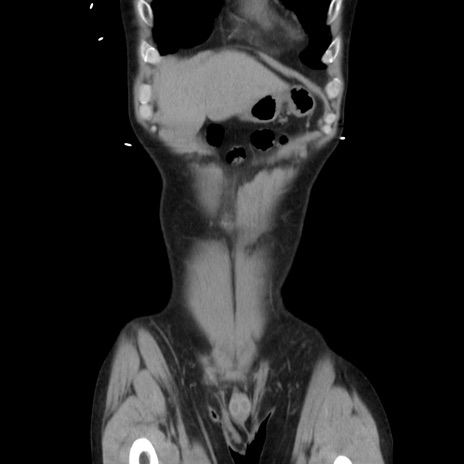

症例37(冠状断像)

【症例】40歳代 男性

【主訴】腹痛

【現病歴】4時間ほど前に電車に乗車中に臍部上より腹痛出現。徐々に増悪し起立困難となり、救急外来受診。生ものは数日食べていない。今朝お雑煮を食べた。

【身体所見】BT 36.8℃、BP 117/84mmHg、HR 91/min、SpO2 97%、苦悶様、腹部:臍上部広範囲圧痛あり、反跳痛±

【データ】WBC 8100、CRP 0.03